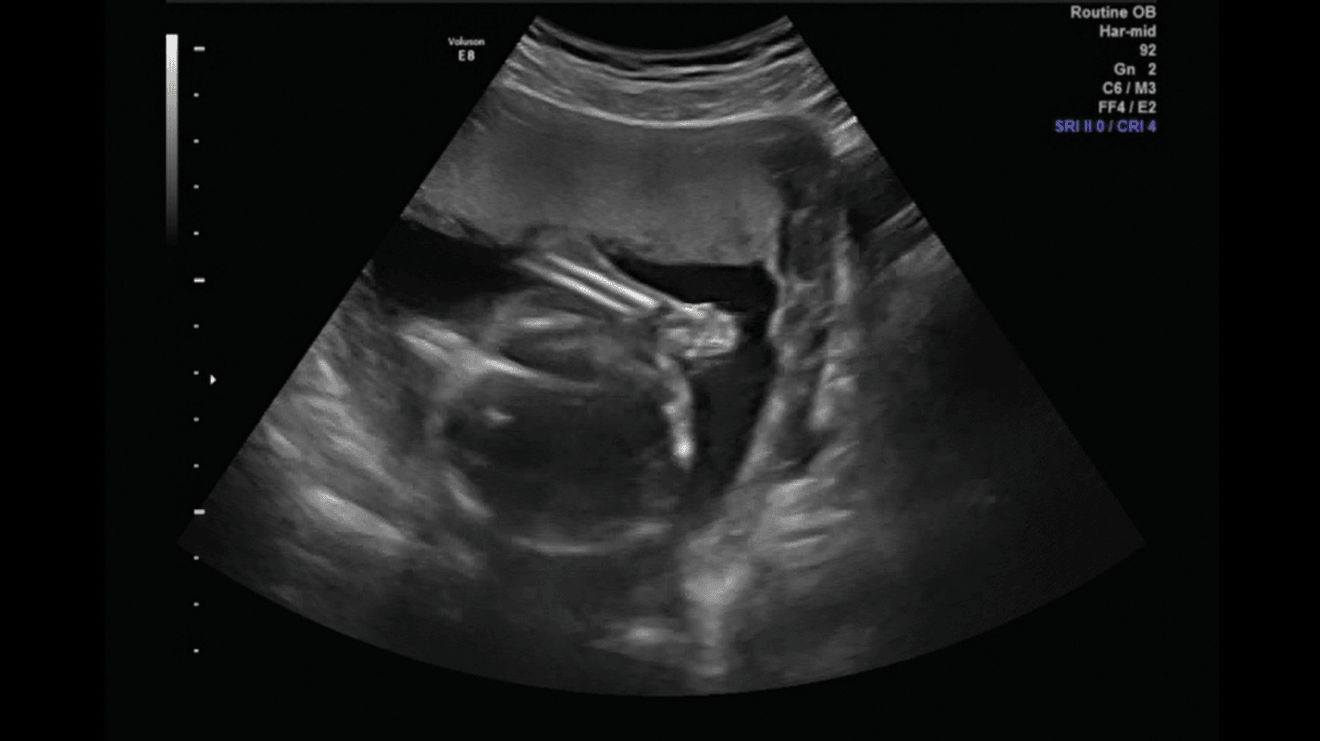

Porobiłam trochę screanów z usg połówkowego, więc pomyślałam, że wrzucę, mam nadzieję, że nie maci mi za złe ilości :D

Pupcia [emoji8]

4.png